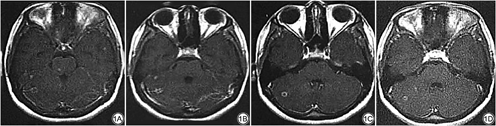

本研究中MRI影像学图片显示治疗6个月后患者的病灶数、病灶大小均减少,治疗6个月内病灶的消失率为71.59%(5767/8056)。当病灶直径较大时MRI表现为环形病灶,可以是规则的圆形或类圆形,也可以是不规则的环形。结节状病灶影像学表现为均质性实性结节,直径或大或小,磁共振T1加权图像呈等或略低信号,T2加权图像呈等或略高信号[14, 15]。环状病灶影像学表现为脑实质内由外周环状结构和不同信号的中心结构组成,代表病理上肉芽肿的环和干酪样坏死的中心,磁共振T1加权图像中心为低信号,肉芽肿环成等信号或略高信号,T2加权图像中心为低信号,干酪样坏死中心表现为低信号[16, 17]。提示MRI检查可清晰地显示治疗过程中病灶的类型、分布情况、大小,能够为颅内结核治疗效果的评估提供参考依据。同时研究发现,治疗6个月后患者的脑脊液蛋白、葡萄糖、脑脊液腺苷脱氨酶水平低于治疗前,白细胞计数、单核细胞、中粒细胞计数、颅内压、淋巴细胞计数、氯化物水平高于治疗前,与Wang等[18]研究一致,说明脑脊液中细胞学分析可预测结核性脑膜炎的病情进展,作为疗效评估的依据,当结核菌侵袭蛛网膜或脉络膜时,导致血管通透性增加,颅内压升高,结核菌在脑脊液中繁殖,需要消耗葡萄糖和氯化物,导致葡萄糖和氯化物减少,脑脊液中蛋白含量增加,加剧脑脊液循环通道粘连的风险[19, 20, 21, 22]。且研究还发现,治疗6个月后MRI检查显示316例治愈,占比79.00%,脑脊液检查显示298例治愈,占比74.50%,两者检查结果比较差异无统计学意义, Kappa值=0.595,提示MRI和脑脊液的动态监测对病情的评估和治疗效果的诊断一致性较好,临床治疗可以结合两种检测方式综合评估。

MRI影像学图片显示治疗6个月后患者的病灶数、病灶大小均减少(P<0.05),其中400例患者共检出8056个病灶,粟粒型病灶2988个,结节型病灶5068个。治疗6个月内病灶的消失率分别为96.32% (2878/2988)、57.00% (2889/5068),总的病灶消失率为71.59% (5767/8056)。见表1。

治疗前后患者的MRI影像学指标变化

| 时间 | 病灶数(个) | 病灶大小(cm) |

|---|---|---|

| 治疗前 | 20.14±4.12 | 0.78±0.23 |

| 治疗后 | 13.15±2.19 | 0.26±0.11 |

| t值 | 29.962 | 40.792 |

| P值 | <0.001 | <0.001 |